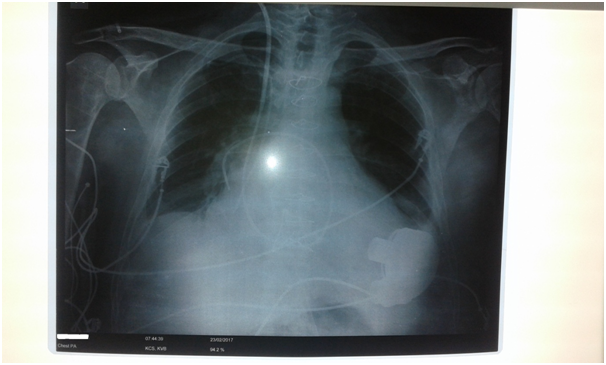

The postoperative course at the clinic for cardiac surgery also regular. The pump speed was set at 4800 rpm, PF 3,4, PP 3,2, PI 3,3, Hct 27.Stable LVAD parameters and data from the controller. Auscultation shows cardiac rhythmic action, clear sound of LVAD pump without variations in intensity. Laboratory and radiological analysis within the reference values (Figure 2). The echocardiography at discharge showed the left ventricle increased in size, smaller in (EDD 6.6, ESD 5.7 cm), normal wall thickness. A slight MR 1+ is recorded into the left atrium with dimensions of 4.6 cm. The right ventricle was of smaller dimensions comparison to the preoperative findings of 2.6 cm, better systolic and longitudinal functions. There was still the presence of TR 1-2+ of eccentric stream directed towards the DP wall. A mild PR 1+ was recorded. The input and output cannulas of device were with excellent colors with the flow rate. The patient and his family were educated regarding the device’s functioning (battery charging, alarm registration) and the hygiene of the output area of the drive line. The patient no showed symptoms of heart failure and was physically active. After one month the patient was discharged. On follow-up examination one and two months after discharge, LVAD parameters and data on controller were stable. The LVAD alarms were not registered. The patient was put on the list for a heart transplant.

Figure 2 Radiografic findings after LVAD Heart Mate 3 implantation and tricuspid valve reconstruction.